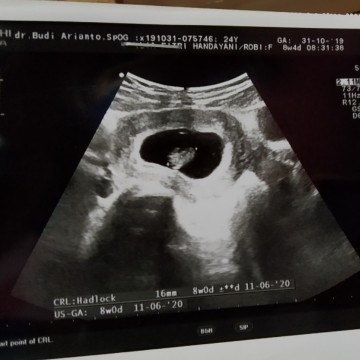

usg

Hasil USG ke dokter

waaa alhamdulillah udah kelihatan. nanti saya juga mau usg pertama 8w.. doain juga ya bun.. semoga debaynya udah kelihatan. dan djjnya udah bisa dideteksi. aamiin

Ini dokter SPOG yg d tempet bu harty praktek ya. ..itu usia brpa week ??

Ini berapa week mom?